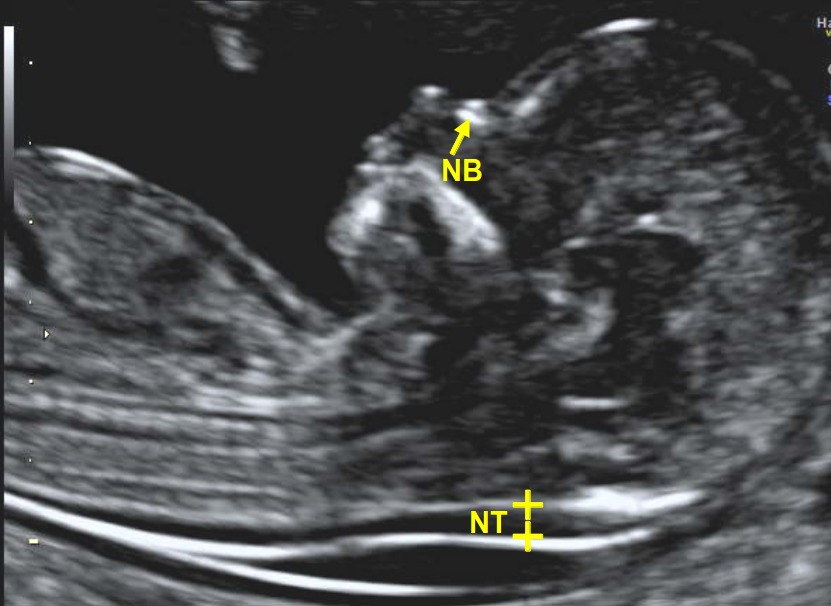

- Measurement of nuchal translucency as part of aneuploidy screening.

Gestational Age: The first trimester ultrasound is crucial for determining gestational age, especially in pregnancies with uncertain LMP dates, irregular menstrual cycles, or those conceived while on hormonal contraception. It provides a more accurate estimation than menstrual dates, influencing management decisions such as the timing for labor induction and cesarean births.

- Assessment of fetal cardiac activity.